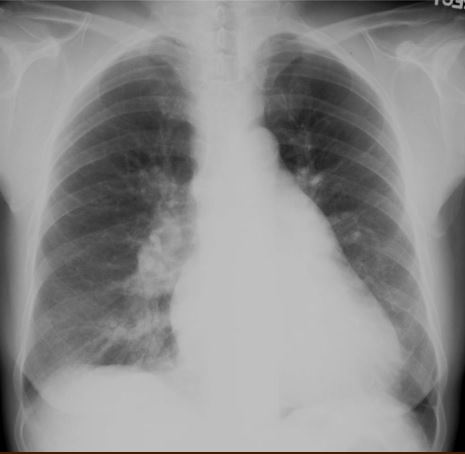

A. Pneumonia

B. Left lung cancer

C. Pleural effusion

D. One lung ventilation